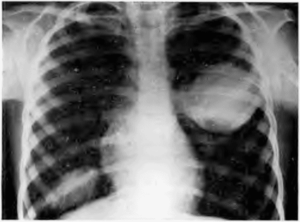

Подтвердить диагноз поможет рентгенография органов грудной клетки.

Рентгенологические данные могут иметь определенные различия и зависят от формы и стадии болезни:

- При центральной локализации патологического процесса на рентгенограмме выявляются прикорневые инфильтраты разного размера.

- При субплевральных очагах выявляется только утолщение участка плевры.

- В стадии инфильтрации над поверхностью легких определяется снижение прозрачности легочного рисунка, затем плотность затенения возрастает, и становится виден инфильтрат неправильной формы с размытыми контурами и радиальной тяжистостью по периферии.

- Стадия абсцедирования характеризуется наличием очагов деструкции в пораженном легком с перифокальным воспалением и усилением легочного рисунка в здоровом легком.

- Нередко после прорыва абсцесса в паренхиме легких формируются плевролегочные полости с горизонтальным уровнем жидкости.

Рентгенологическое исследование в ранней стадии выявляет очаговые инфильтраты вокруг бронхов и сосудов, увеличение медиастинальных лимфатических узлов и содружественное поражение ребер или позвонков; характерно уплотнение плевры. Процесс может ограничиваться одним сегментом или захватывать целую долю. Течение болезни длительное, при отсутствии лечения развиваются кахексия и анемизация больных.